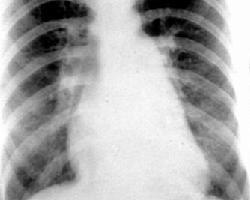

高原肺水肿是指近期抵达高原(一般指海拔3000米以上),出现静息时呼吸困难、胸闷压塞感、咳嗽、咳白色或粉红色泡沫痰,患者感全身乏力或活动能力减低。